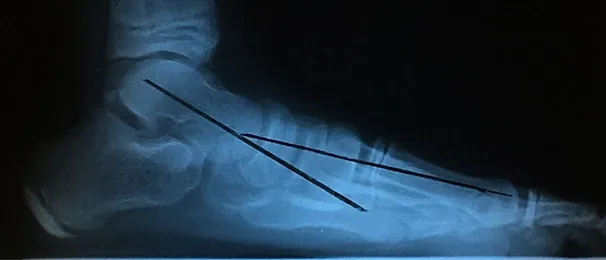

Pre and Postop X-rays Subtalar Joint Implant (Below)

Patient JD